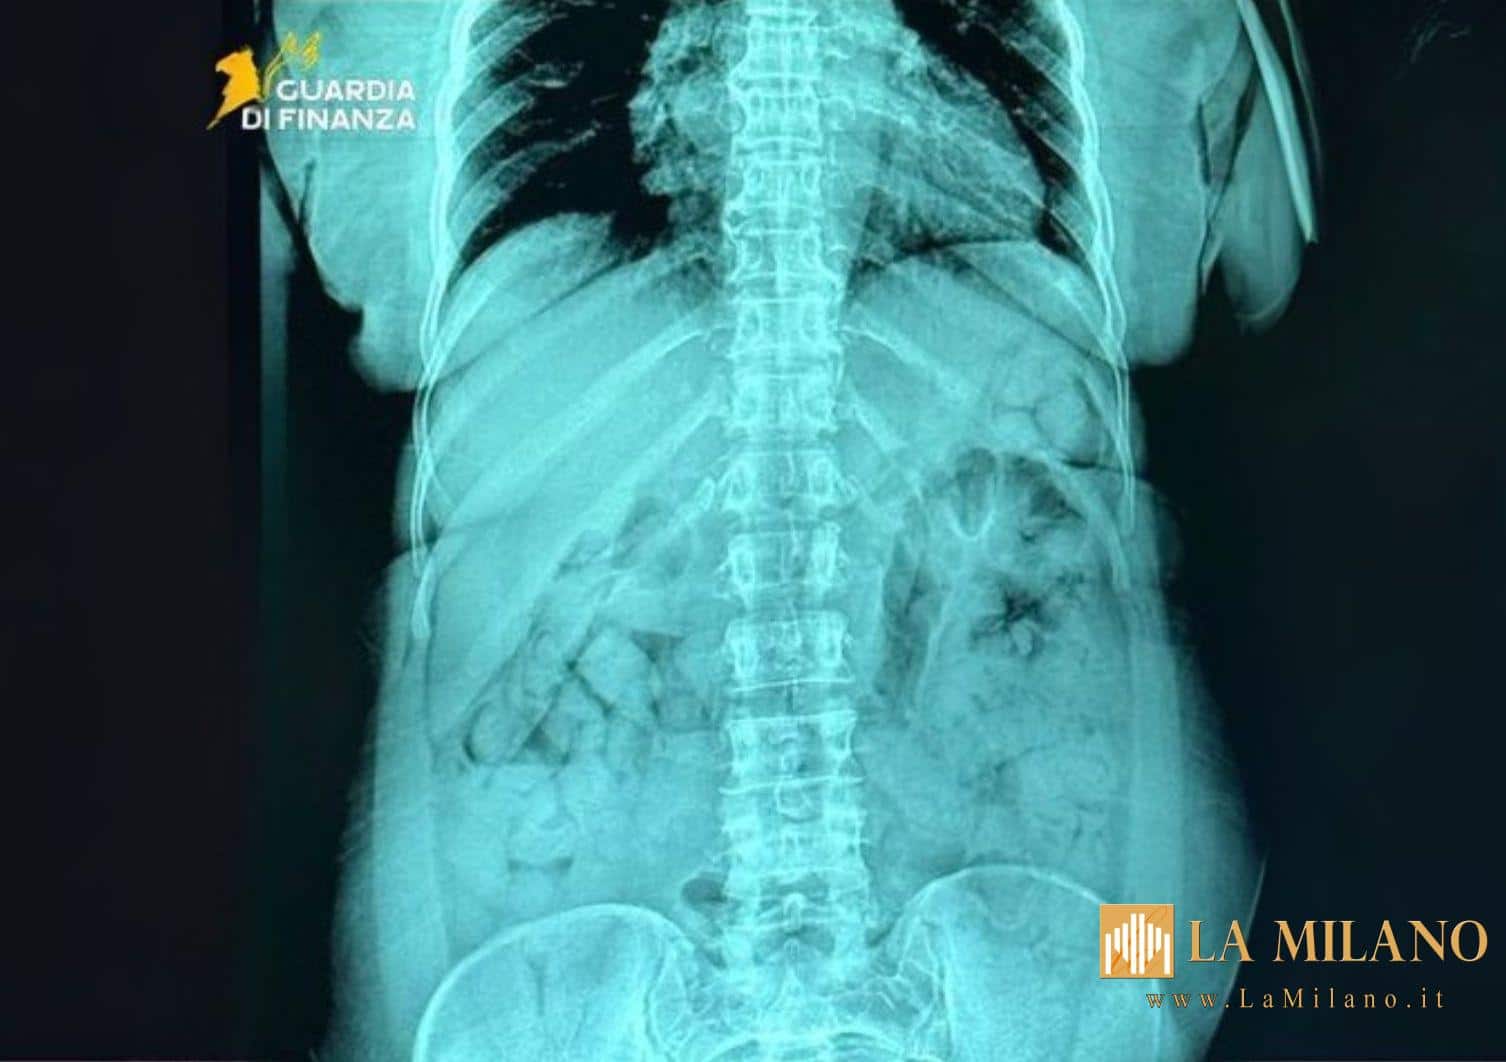

I successivi esami radiologici svolti presso l’ospedale “Papa Giovanni XXIII” di Bergamo hanno confermato che la viaggiatrice aveva ingerito 120 ovuli in contenitori plastici rigidi avvolti in strati di nastro adesivo i quali, una volta analizzati, sono risultati contenere sostanza stupefacente del tipo eroina, per complessivi 1.393 grammi.